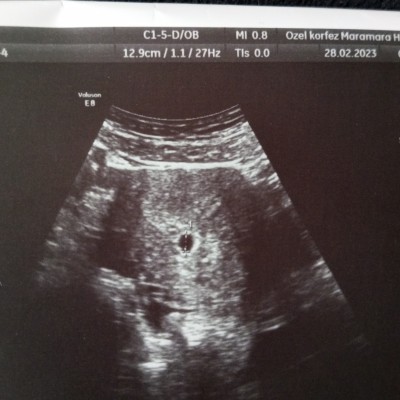

İlk muaynemde (özel) kesen ortada biraz daha üstte olması lazım dedi ve düşük riski tanısıyla bu ilacı verdi kullandım 1 kere ama ben de emin olamadım ve başka bır doktorada (devlet) göründüm ve bu ilacı kullanmama gerek olmadığını kullanmamamı şuanda her şeyin normal olduğunu söyledi. sonrasında başka uzman bir doktora (özel) sordum iki hastanede çekilmiş ulturasonları gösterdim normal olduğunu düşük riskim olmadığını fakat ilaca başladıysan devam et bırakırsan kanaman olur falan

dedi böyle bir şey yaşayan var mı ne yapmalıyım yani kullansam da sorun olmaz diye düşünüyorum

Gebelik haftası 5